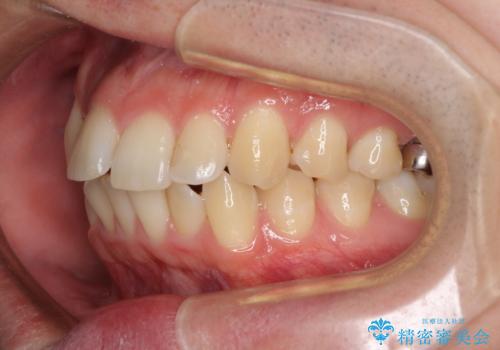

- 上下前歯のデコボコを気にして来院された患者様です。

マウスピース矯正でもワイヤー矯正でも対応可能でしたが、インビザラインによる自己管理が煩わしいとのことで、ワイヤー装置にて矯正治療を行うこととしました。

口元はやや突出感がありましたが抜歯矯正をするほどではないため、舌突出癖を改善するトレーニングをしっかりと行っていただき、現在よりも唇が閉じやすい位置に仕上げていくこととしました。

下顎前歯が思っていた以上に動きが悪く、想定よりも期間がかかってしまいました。

矯正治療後には気になっていた銀歯をセラミックで自然な色に仕上げました。